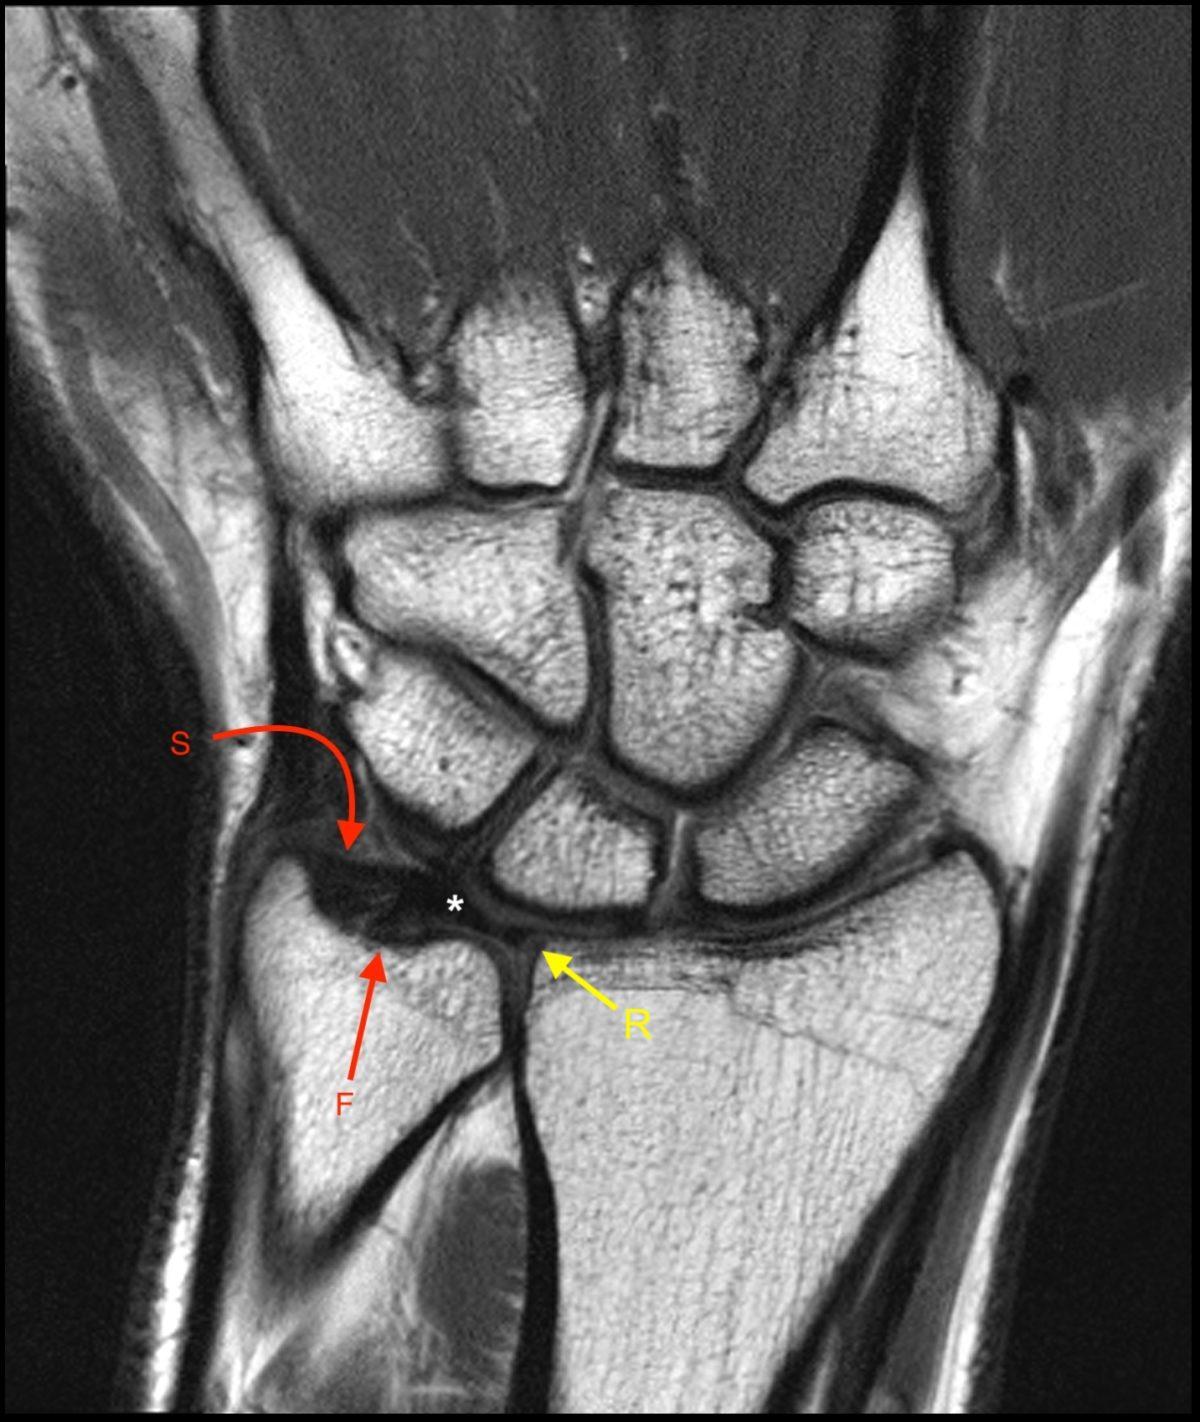

Understand the causes, symptoms, and treatment options for dinner fork deformity. This characteristic wrist displacement often indicates a distal radius fracture, commonly known as a Colles' fracture. Learn how orthopedic specialists diagnose this injury, the importance of prompt medical intervention, and effective recovery strategies to restore proper wrist alignment and full range of motion after trauma.

TitleDistal End Radius Fractures - Colles, Smiths & Bartons | PPTX